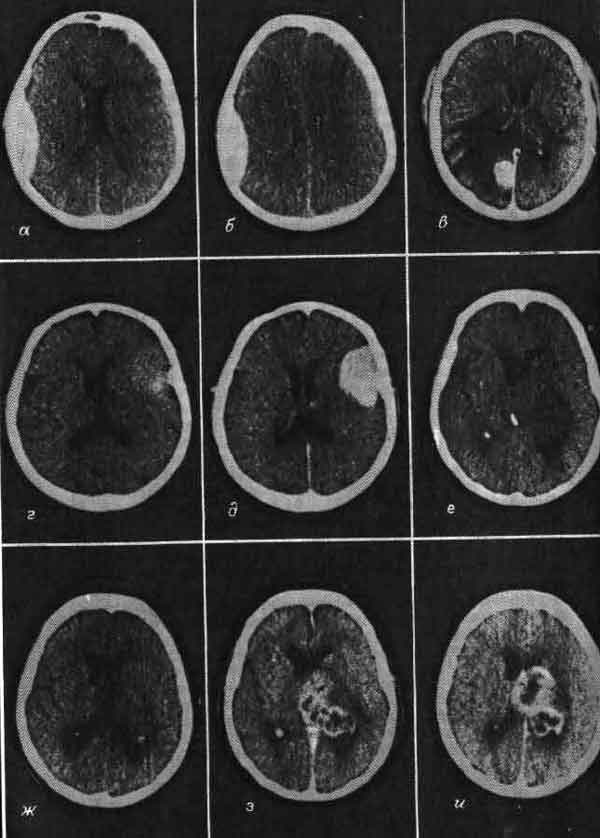

Последним в этом ряду достижений явилась методика, разработанная несколько лет назад Л. Соколовым (L. Sokoloff) в Национальном институте охраны психического здоровья. Глюкоза служит «топливом» для нейронов и в активном состоянии клетки потребляют больше глюкозы, чем в покое. Меченая дезоксиглюкоза усваивается клетками, как если бы это была глюкоза. Она расщепляется, как глюкоза, но продукт первого этапа ее метаболизма не подвергается дальнейшим превращениям. Не имея поэтому возможности выйти из клетки, этот продукт скапливается в ней, и степень радиоактивности в определенных клетках указывает на их функциональную активность. Можно поставить, например, такой опыт: ввести это вещество внутривенно лабораторному животному, а затем предъявить звуковой раздражитель; микроскопическое исследование мозга позволит выявить те его области, которые связаны со слухом. Совсем недавно разработана новая методика-позитронно-эмиссионная томография, которая позволяет обнаруживать с помощью наружных датчиков присутствие дезоксиглюкозы или других веществ, меченных радиоактивными изотопами, испускающими позитроны. Эта перспективная методика делает возможным картирование активных структур мозга in vivo у лабораторного животного или у человека.